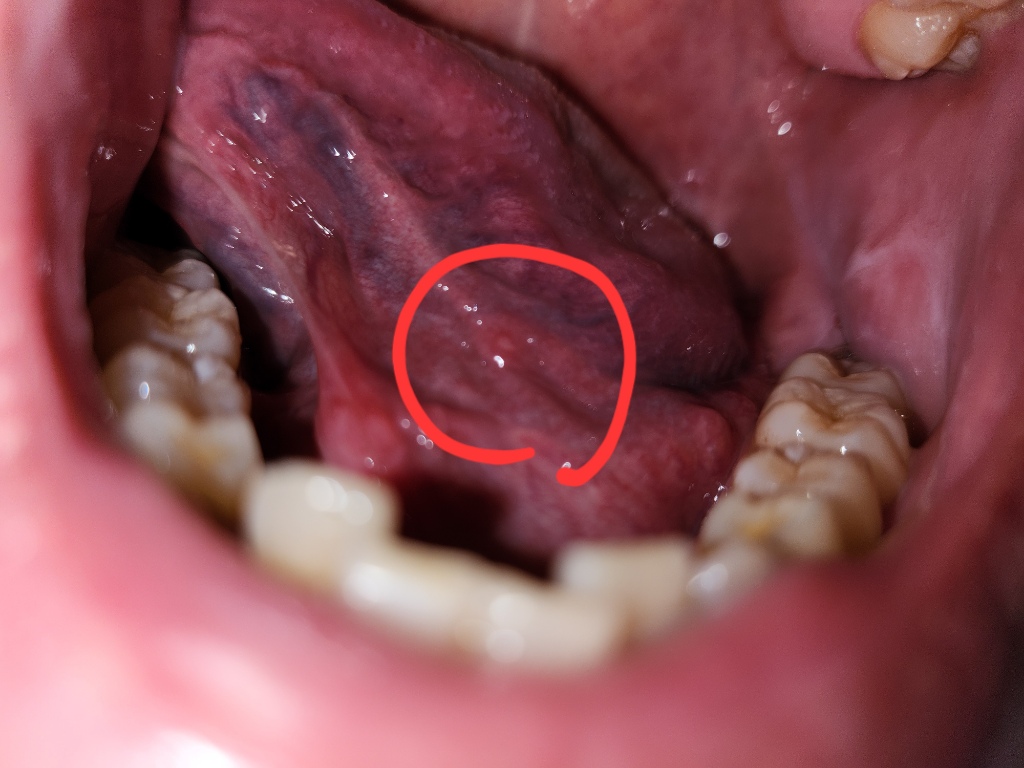

안녕하세요. 송우식 치과의사입니다.

현재 구내염으로 보이며, 우선 충분한 휴식과 영양섭취를 하고, 소독용 가글인 헥사메딘이나 탄툼가글액으로 가글을 하길 권합니다. 만약 오래 지속되거나 크기가 커지거나 통증이 동반되는 경우 치과 진료를 받길 권합니다.

혀밑에 일종의 구내염처럼 물집이 잡힌것 같습니다. 시간이 지나면 괜찮아 질꺼 같으니 너무 걱정은 안하셔도 될것같습니다.